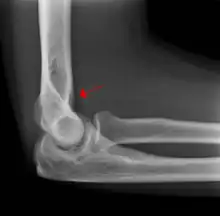

The fat pad sign is invaluable in assessing for the presence of an intra-articular fracture of the elbow. An anterior fat pad is often normal. However a posterior fat pad seen on a lateral x-ray of the elbow is always abnormal. The patient will be unable to flex their elbow and requires orthopaedic input.[2]

The posterior fat pad is normally pressed in the olecranon fossa by the triceps tendon, and hence invisible on lateral radiograph of the elbow.[3] When there is a fracture of the distal humerus, or other pathology involving the elbow joint, inflammation develops around the synovial membrane forcing the fat pad out of its normal physiologic resting place. This is visible as the "posterior fat pad sign" and is often the only visible marker of a fracture, particularly in the pediatrics population.